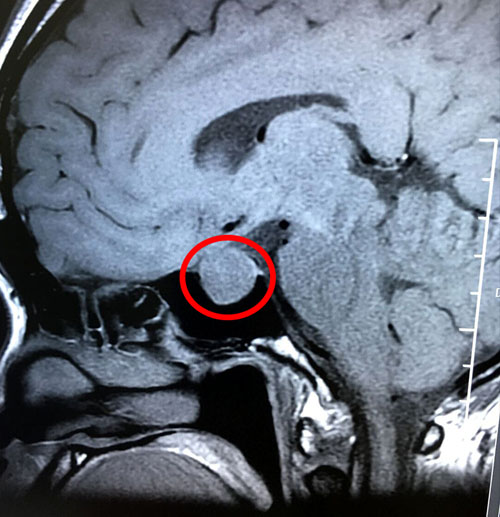

在医院神经外科潘仁龙主任的安排下,郑钰玲又做了检查,发现垂体瘤又长大了,大小是1.9*1.5*1.7公分,而且超蝶鞍生长。完善血尿常规,生化,凝血,心电,彩超等各项检查之后,未发现手术禁忌。潘仁龙主任和李士其教授又进行了会诊和术前讨论。

术前影像:垂体大腺瘤,超蝶鞍生长